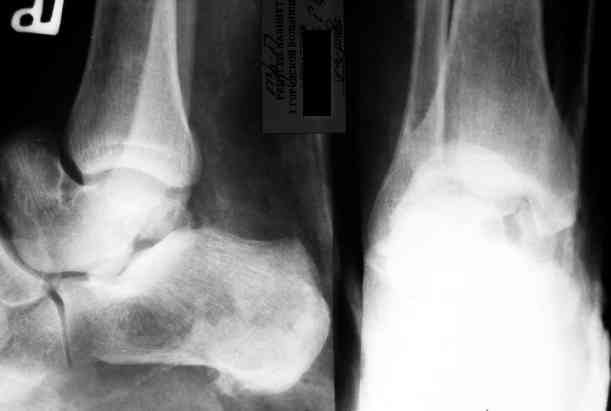

Уважаемый Александр! Как обещал представляю Р-граммы и операционные фото.

Опять надоедаю с вопросами:

Ваши (лично ваши) рекомендации - астрагалэктомия-аппаратный пяточно-большеберцовый артродез с одновременным удлинением голени - правильно?